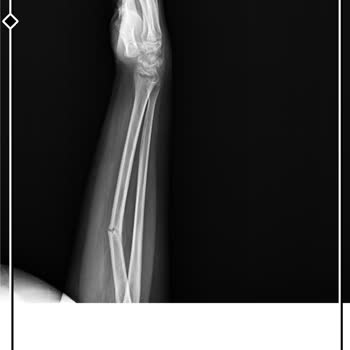

5 Eylül 2025 tarihinde saat 11.10 sularında yaşadığım bir kaza sonucu elimde kesikler oluştu ve f. S. M Hastanesi acil servisine başvurdum. Elim kanarken, acil serviste yaklaşık 1 saat bekletildim ve 1 cm’lik açık kesik ancak 1 saat sonra dikildi. Dikişi atan doktor, elim kanar haldeyken ve kesik aç...